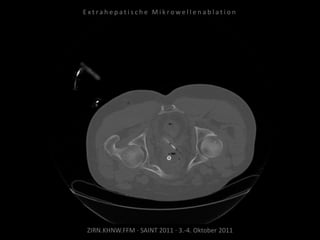

Metastase medial des linken

Musculus iliacus:

1 Nadelposition.

Kontrollbildgebung:

CT 18.08.2010

MRT 08.09.2010

Restvitalität von 2 Metastasen.

Nadelposition unzureichend?